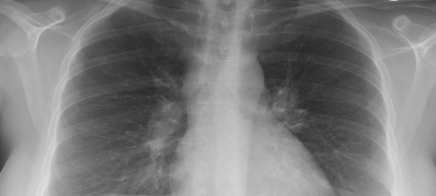

Der Husten führt zur diagnostischen Abklärung der Lunge. Diagnostisch öffnen sich damit neue Fenster. Der behandelnde Arzt entscheidet, welche Schritte zur eindeutigen Diagnose führen.